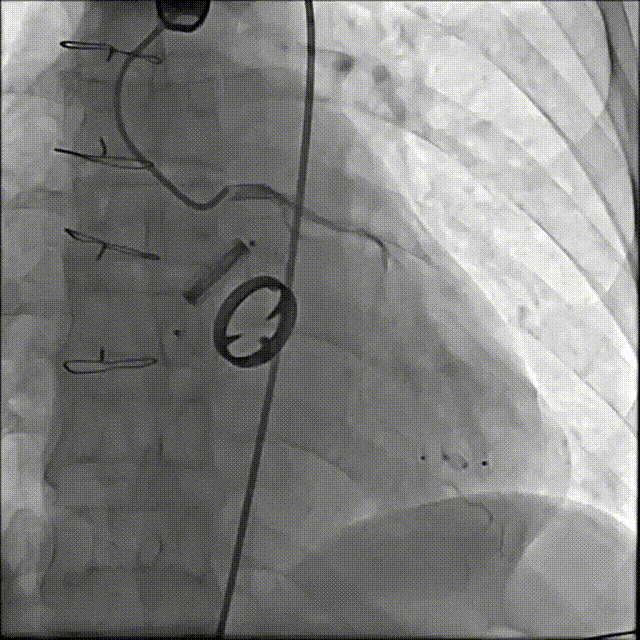

术后封堵器形态位置

手术全程顺利,术中出血100ml,使用造影剂40ml,共计用时1小时50分钟,术后患者无不适,安全返回普通病房,并于3天后出院。